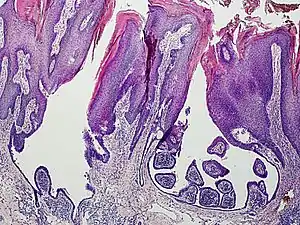

a) Syringocystadenoma papilliferum over a pre-existing nevus-sebaceous b) histopathology of syringocystadenoma papilliferum showing cystic invagination of surface epithelium

An example of a syringocystadenoma papilliferum